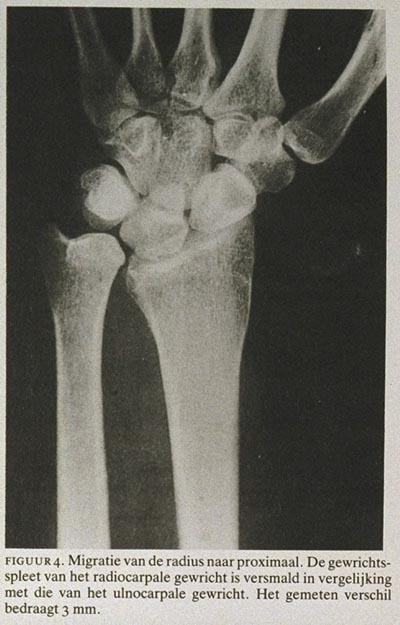

In hun artikel stellen Van Beek, Meijer en De Mol (1986;1797-1800) de gevolgen van een extirpatie van het caput radii aan de orde. Deze extirpatie leidt volgens de literatuur zoals in het betrokken artikel ook is aangehaald tot een voorspelbare verstoring van de stabiliteit van de elleboog en de onderarm. Door het wegvallen van het caput als steunpunt van de radius op het capitellum humeri treedt een proximale migratie van de radius ten opzichte van de ulna op. Als gevolg hiervan ontstaat een zekere subluxatie in het distale radio-ulnaire gewricht. Na verloop van tijd kan dan ook in dit gewricht arthrosis ontstaan. Tevens belemmert de migratie van de radius enigszins de rotaties van de onderarm (vooral de supinatie), waarschijnlijk doordat de membrana interossea onder spanning komt. Wegvallen van het caput als lateraal steunpunt leidt tot meer stress op het mediale bandcomplex van de elleboog en kan pijn veroorzaken. Door tractie aan de N. ulnaris kunnen daarnaast hinderlijke prikkelingen optreden.